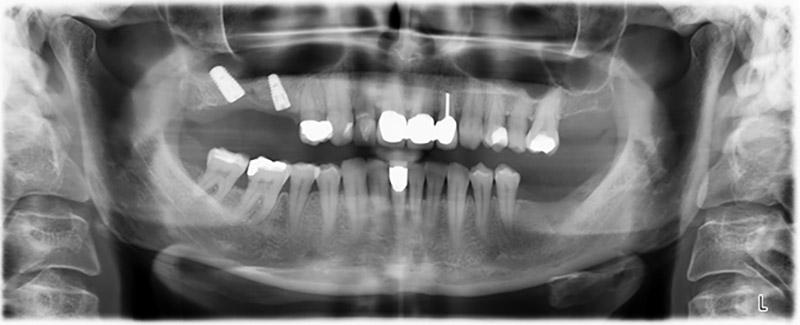

Die 59-jährige Patientin wurde mit einer fortgeschrittenen Parodontitis vorstellig, beschrieb ein ungutes Gefühl und einen schlechten Geschmack ausgehend vom ersten Quadranten distal. Die klinische Untersuchung zeigte allgemein erhöhte Taschentiefen und einen stark fortgeschrittenen Knochenabbau in regio 16 und 14. Die radiologische Untersuchung untermauerte den Befund (Abb. 1). Die Zähne 16 und 14 waren nicht zu erhalten.